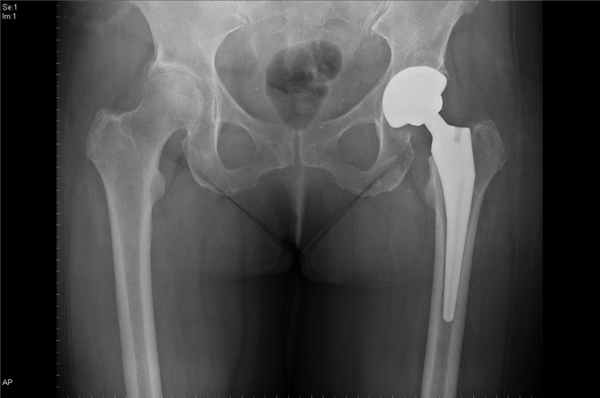

Лечение коксартроза – только хирургическое. В настоящее время это подразумевает эндопротезирование пораженного тазобедренного сустава. Эндопротезирование тазобедренного сустава – это операция по замене поврежденного при болезни или травме сустава искусственным аналогом. В некоторых случаях это единственное средство вернуть человеку способность ходить.

Если консервативные терапия не приносит результатов, на рентгене прослеживается дальнейшее разрушение тазобедренного сустава – необходимы решительные меры. Такие как операция по замене разрушенного сустава. Это хирургическое вмешательство по удалению поврежденного тазобедренного сустава и имплантации на его место искусственного эндопротеза. Он идеально повторяет форму сустава и после восстановления полностью принимает на себя объем движений. Таким образом при запущенной стадии артроза эндопротезирование является единственным способом восстановить движение в суставе.

При коксартрозе 3 степени на рентгене видно значительно суженую суставную щель. Болевые ощущения интенсивные, сустав деформируется – развивается дефартроз тазобедренного сустава. На таком этапе, как правило, нехирургические методы лечения неэффективны. Необходима замена тазобедренного сустава (эндопротезирование).

Сустав полностью разрушен, мышцы атрофированы, боль в суставе беспокоит пациента практически постоянно. Единственный способ решить проблему с суставом – провести эндопротезирование тазобедренного сустава.